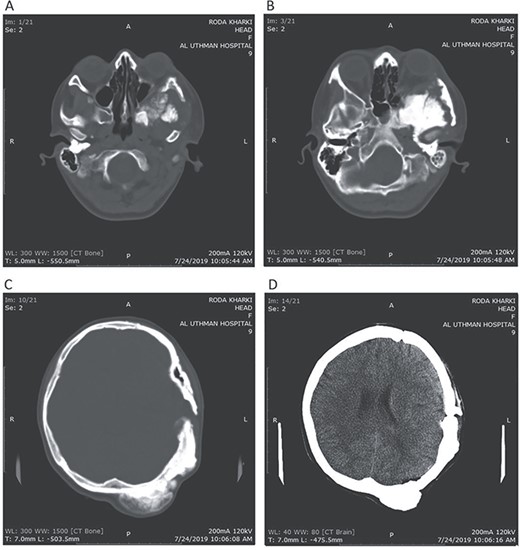

CT head tissue window (A, B). A. Invasion of the maxillary sinus and orbit. B. Invasion of the parietal, temporal and frontal lobes. A remarkable exophthalmos. Bone window (C, D). C. The bone-forming lesion showing the same density of the bone. D. Invasion of the sphenoid, temporal and parietal bones.

A 17-year-old female presented with a history of osteosarcoma that was confirmed after undergoing a surgery to remove an enlarging bone tumor in the left temporal region 2 years ago. She later got pregnant and delivered her child but never got back for a checkup until she was admitted to our hospital with a severe and unresponsive to medication headache that progressed over the course of 6 months and blurred vision that progressed to complete left-sided vision loss. Physical examination revealed a tough and mobile yet fixed at the base 7-cm mass towards the left of the frontal bone. Many more masses were revealed in the left side of the skull including the anterior cranial fossa, orbit, base of the skull and the left part of the occipital region where the previous procedure was performed (Fig. 1). These masses had been increasing in size probably under the influence of pregnancy hormones causing pain that radiated along the orbital and maxillary branches of the left trigeminal nerve. Physical examination and past medical history were otherwise unremarkable. Laboratory tests were all normal, and her family history was negative. Staging studies showed no evidence of distant metastatic disease in the chest, the abdomen and the pelvis. CT scan of the skull revealed a bone-forming non-lytic lesion accompanied by periosteal reaction. This lesion bulges to the outside towards the scalp spreading into both the soft tissues and the inside of the entire left side of the skull with a sunburst-pattern (Figs 2 and 3). Its rims are unsymmetrical and pointy, and it bulges into the left orbit outside the muscles causing exophthalmos with a semi-complete proptosis of the eyeball out of the orbit (Figs 2 and 3). This lesion applies pressure to the left frontal and temporal lobes causing mild edema in both these lobes without invading the brain tissue. This edema in turn applies pressure to the left lateral ventricles (minor shift of the elements of the midline to the right side can be seen on CT) (Fig. 4). Due to the tumor’s wide spread, the surgical procedure was performed in two stages (approximately 6-hour-long each). In the first stage, the bone mass was removed through a procedure of wide skull approach including the frontal, temporal and parietal bones and a removal of the invading part of the temporal muscle. Moreover, the lateral wall and roof of the left orbit were removed, the left optic nerve was dissected free and part of the meninges was removed and replaced with an autogenic patch from the fascia lata. Then, the bone loss was compensated for by using bone cement Synicem VTP (poly methyl methacrylate and Barium sulfate), and the orbit was rebuilt; the eyeball was placed back with noticeable decline of the exophthalmos. In the second stage, a complementary left parietal occipital incision of the previous approach was performed 3 weeks later; the remaining of the frontal and occipital bones was removed, and a partial mastoid surgery was done. Furthermore, the cavernous sinus were revealed and found to be not invaded. Later on, the normal skull shape was restored using the same cement. The histopathology of the lesion revealed proliferation of neoplastic chondroblasts, osteoblasts and spindle-shaped cells. The features are consistent with low-grade chondroblastic osteosarcoma (Fig. 5). The patient did not need ICU admission. She recovered well 3 days after the surgery and was discharged with no deficits. A CT scan that was performed post-operatively revealed that the masses were successfully excised (Figs 6 and 7). At the last follow-up 1 month post-operation, the patient was scheduled to undergo a course of radiotherapy, 60 Gy of radiotherapy in 30 fractions over 4 weeks without chemotherapy, as it is not recommended with low-grade osteosarcoma.